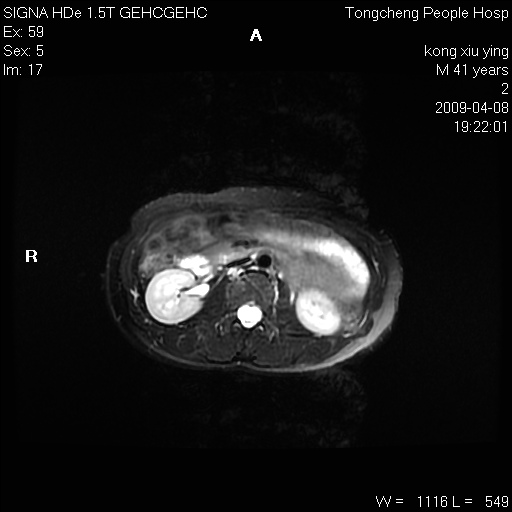

标题: CL1008:【经典】胆囊石榴籽样结石。

女,41岁。健康体检——彩超提示:胆囊显示不清。平素健康,无不适感。

腹部mr扫描及mrcp,图像如下: